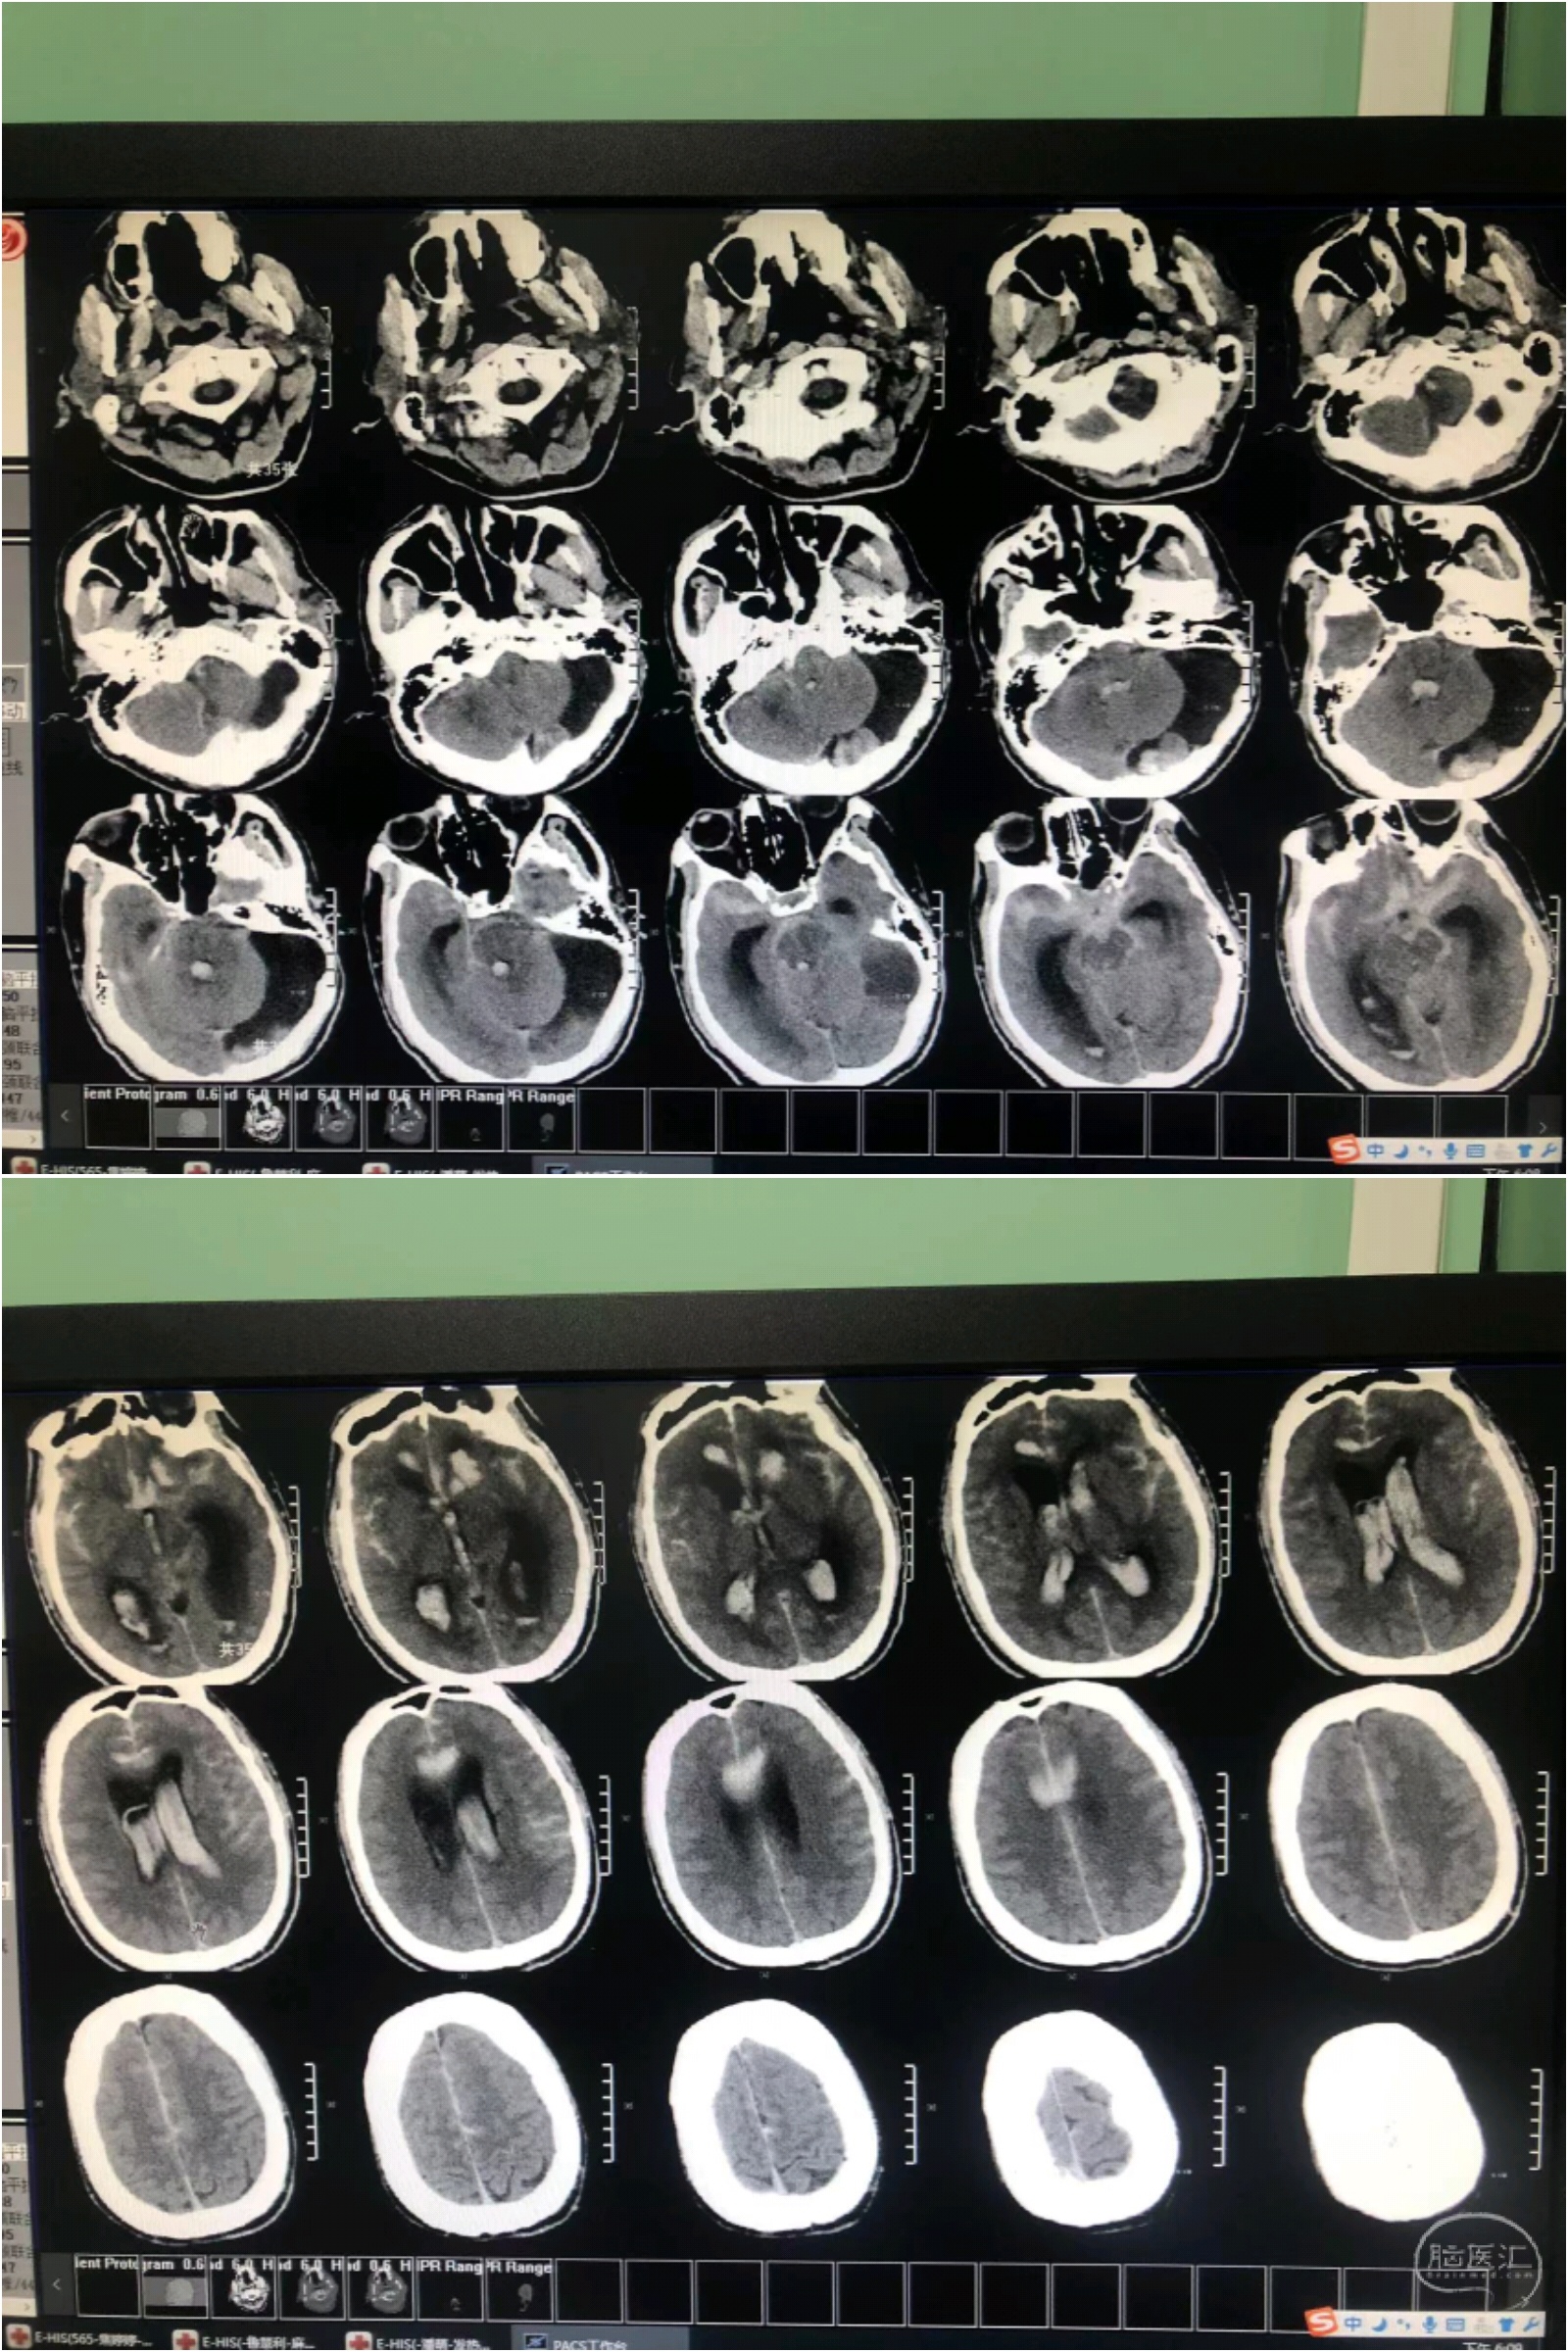

48岁男性,蛛网膜下腔出血。入院后意识水平由清楚逐渐呈轻度浅昏迷,HH分级由2级上升至4级,出血量增加。术前WFN分级IV级,改良Fisher分级IV级。治疗方案:动脉瘤介入栓塞+双侧侧脑室引流。方案既定,治疗紧张而有序的实施。

计算:动脉瘤直径:2.98*2.38,瘤颈1.71mm 预计填入弹簧圈长度:2.98*2.38*1.26大约9厘米。

实际:首枚圈2.5*4 3D,成篮良好;第二枚2*3 2D;第三枚1*1。见动脉瘤致密栓塞,栽瘤动脉通畅,瘤颈也不显影,栓塞满意,撤出栓塞及支架微导管。

术后正侧位造影:动脉瘤栓塞满意,有一环突入前交通,无需特别处理,不会影响血流。

介入手术结束后,不醒麻醉,立即请神经外科双侧侧脑室引流,后送入神经重症深度监护治疗。